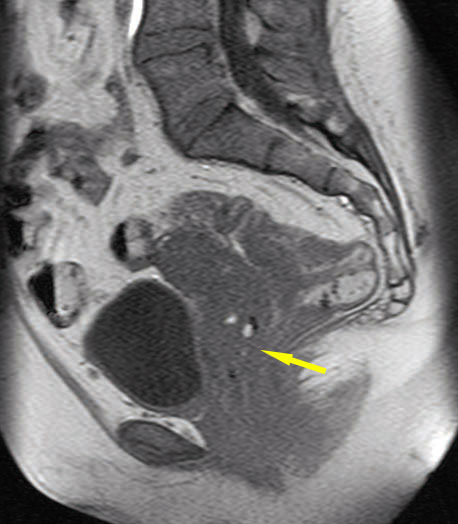

Imagerie par résonance magnétique, en coupe sagittale, en pondération T1, montrant des spots hyperintenses focalisés témoignant d’implants hémorragiques localisés dans le cul-de-sac vaginal postérieur.